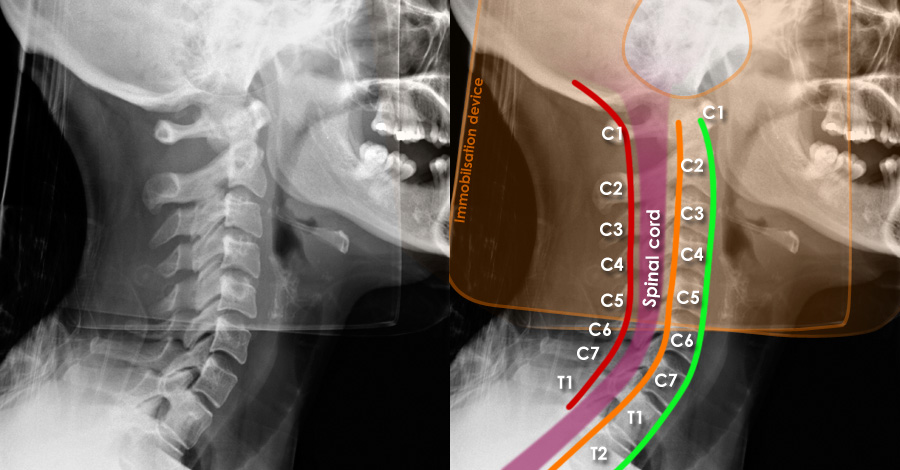

Doctors performed detailed imaging of the cervical spine and found a rare type of injury affecting two vertebrae. This kind of injury does not fit neatly into common medical classification systems, making it a unique case for medical professionals and researchers to study.

Doctors noted that this type of injury pattern is extremely uncommon. It highlighted how even a single falling object can cause serious harm and how important it is for medical teams to be aware of unusual injury presentations that may not match typical guidelines.

The incident also pointed to the need for ongoing review and improvement of classification systems used to understand and diagnose spinal injuries, ensuring that rare cases are better recognized in the future.